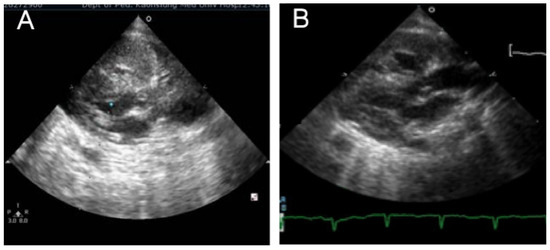

3.1. Case 1

3.2. Case 2

3.3. Case 3

3.4. Case 4

3.5. Case 5

3.6. Case 6

3.7. Case 7